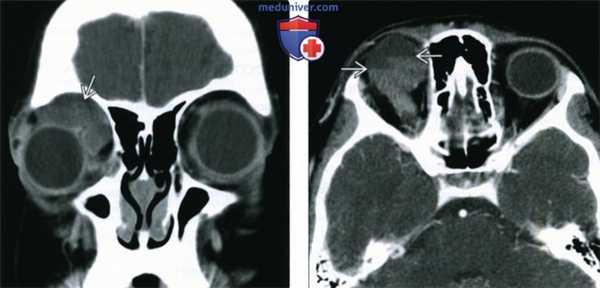

2. КТ при меланоме глаза:

• КТ без контрастного усиления:

о Солидное объемное образование мягкотканной плотности

о Кальциноз наблюдается редко; может развиваться после проведения лечения

• КТ с КУ:

о Диффузное умеренное контрастирование

3. МРТ при меланоме глаза:

• Т1 ВИ:

о Слегка или выражение гиперинтенсивна по сравнению со стекловидным телом:

- Сигнал усиливается при увеличении меланотической пигментации

о Отслойки сетчатки со скоплением субретинальной жидкости: вариабельно гиперинтенсивны в зависимости от наличия белка и продуктов распада крови

• Т2 ВИ:

о Выраженно гипоинтенсивна по сравнению со стекловидным телом

о Субретинальная жидкость: изо- или гипоинтенсивна в зависимости от характера экссудата

• Т1 ВИ с КУ:

о Умеренное диффузное контрастирование опухоли

о Отслоенная сетчатка и субретинальная жидкость не контрастируются

(Слева) При МРТ Т2 ВИ в аксиальной проекции отмечается выраженная гипоинтенсивность меланомы хориоидеи.

(Справа) При КТ с КУ в аксиальной проекции в заднем отрезке левого глазного яблока определяется контрастируемая опухоль с необычно крупным экстраокулярным (ретробульбарным) компонентом, вызывающим экзофтальм. Очень крупные размеры этой меланомы и экстраокулярное распространение опухоли являются неблагоприятными прогностическими факторами.